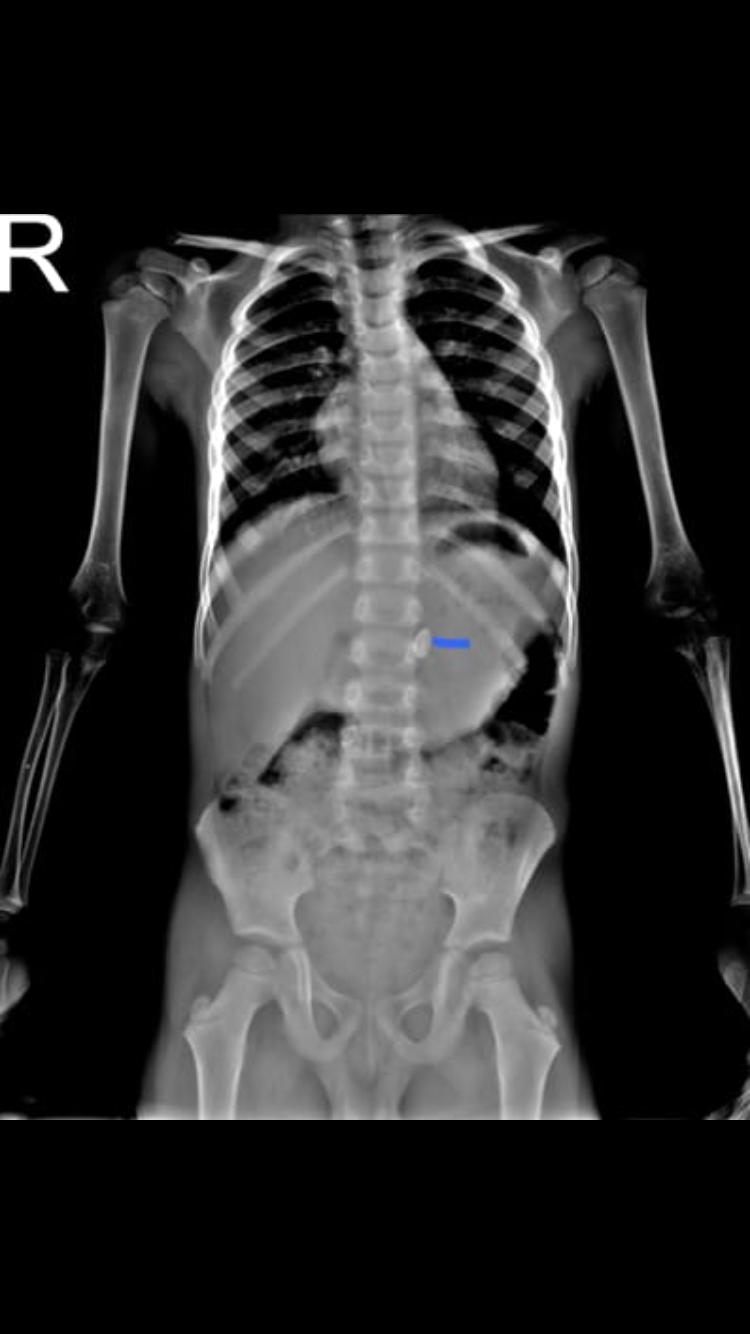

يابنات عندي صوره الاشعه لولدي واضح ان الحديده موجوده

وفي المستشفى يقولون هذي فقره متحركه من العمود الفقري

راسلنا دكتور اطفال وقال ان القطعه الحديديه موجوده ببطنه وحط عليها علامه

هذي الصوره يابنات

هذي العلامه اللي حطها الدكتور وقال هذي القطعه هذي صوره الاشعه في المستشفى اللي يقولون فقره!!

السلام عليكم كيفكم حبايبي جميعاً اسفه مادخلت وطمنتكم يابنات عندي صوره الاشعه لولدي واضح ان الحديده موجوده وفي المستشفى يقولون هذي فقره متحركه من العمود الفقري راسلنا دكتور اطفال وقال ان القطعه الحديديه موجوده ببطنه وحط عليها علامه وقال نراقبه مع البراز الله يكرمكم عشان ممكن تخرج ولو صار امساك او الم بالبطن او قيء نوديه المستشفى فوراً وانا للحين انتظره تطلع 😢 هذي الصوره يابنات هذي العلامه اللي حطها الدكتور وقال هذي القطعه هذي صوره الاشعه في المستشفى اللي يقولون فقره!!